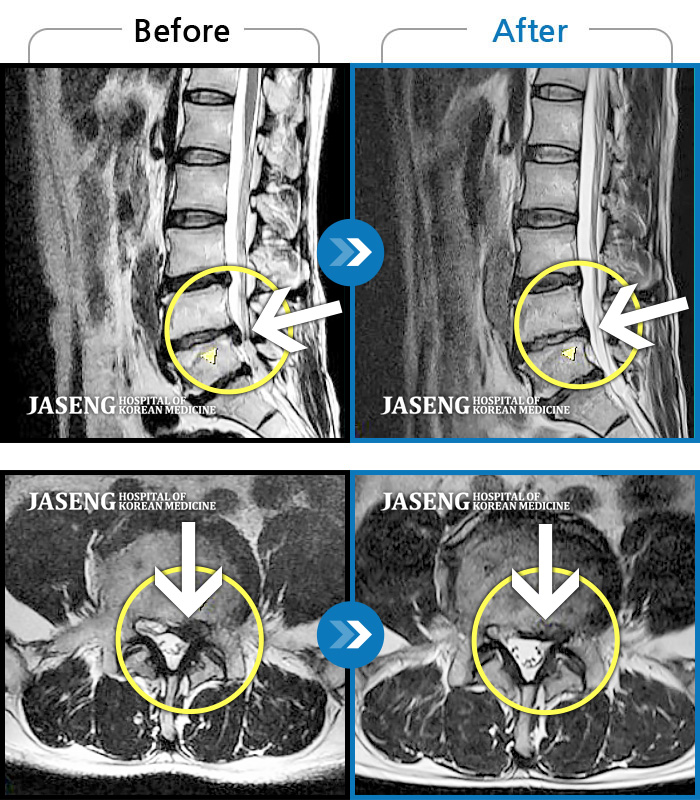

허리디스크

광주 · 장영우 원장

양측 허리의 묵직한 통증 및 기침 시 증상이 심화되어 내원하셨습니다.

촬영시기

2024.12.09 ~ 2025.05.24

2025.06.05